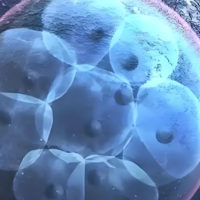

2. 冷冻技术的使用

玻璃化冷冻技术使用卵子/胚胎冻结生存率达96%以上,为跨境治疗提供时间弹性。建议尽早完毕取卵/男性生殖细胞体冷冻,避免频繁往复。